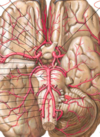

Identify the indicated anatomical features.

- Ventral aspect of the brain, and the aa that comprise the Circle of Willis, the structure that provides potential for collateral blood flow if one or more of the 4 major aa supplying the brain is obstructed/occluded

1. Comprised of PCA connected to ICA via post communicating aa; anterior segment of ACA, called A1, and anterior communicating artery complete the circle - O/important aa here incl. basilar artery, superior cerebellar artery, middle cerebral artery, lateral striate arteries, the vertebral arteries, the superior, anterior inferior and posterior inferior cerebellar arteries